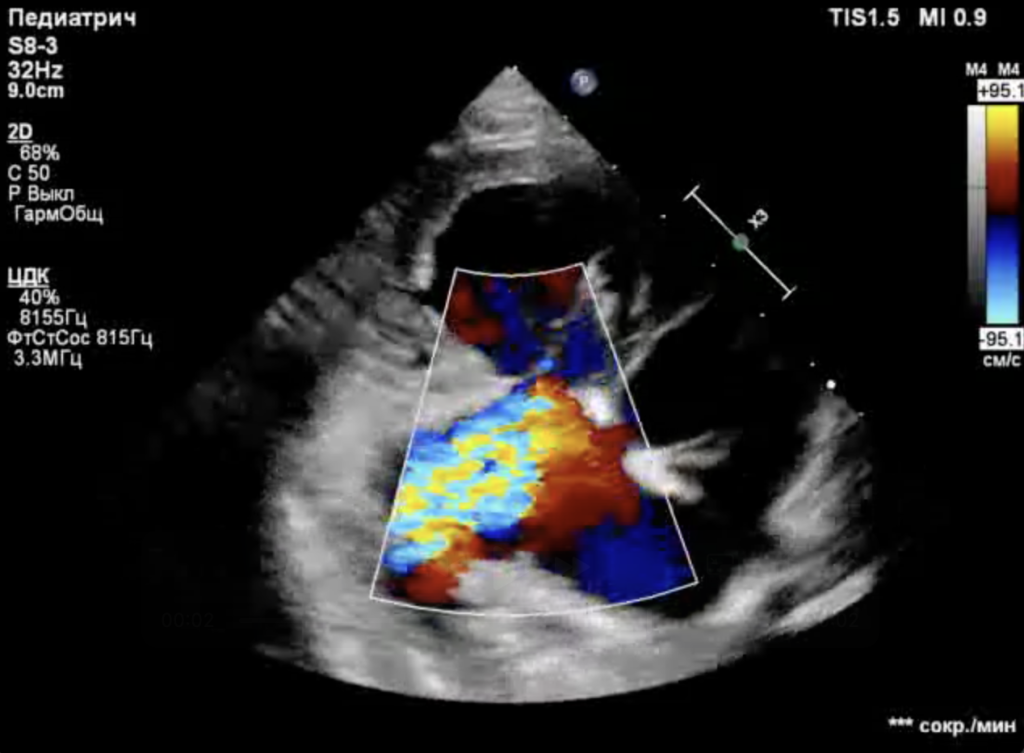

Собака находилась под наблюдением с 5-месячного возраста. При эхокардиографическом исследовании были выявлены следующие аномалии (фото 1-3):

- Выраженная дилатация правого предсердия (47 мм) и правого желудочка (конечный диастолический размер – 34 мм).

- Неделаминированная и малоподвижная септальная створка.

- Укороченные хорды.

- Выраженная регургитация (massive).

- Гепатомегалия, обусловленная застоем крови в системных венах.